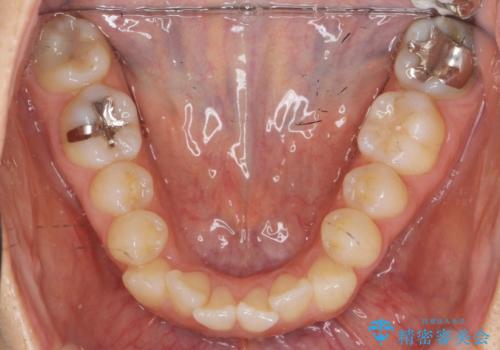

前歯のがたつきをしっかり治すマウスピース矯正

- 前歯のガタガタをきれいに並べたい、と希望され来院されました。

マウスピース矯正インビザラインのクリンチェックを用いて治療前にしっかりと歯並びのゴールのシミュレーションを行い、治療を開始します。

がたつきのないきれいな歯並びに仕上げることができ、満足いただくことができました。